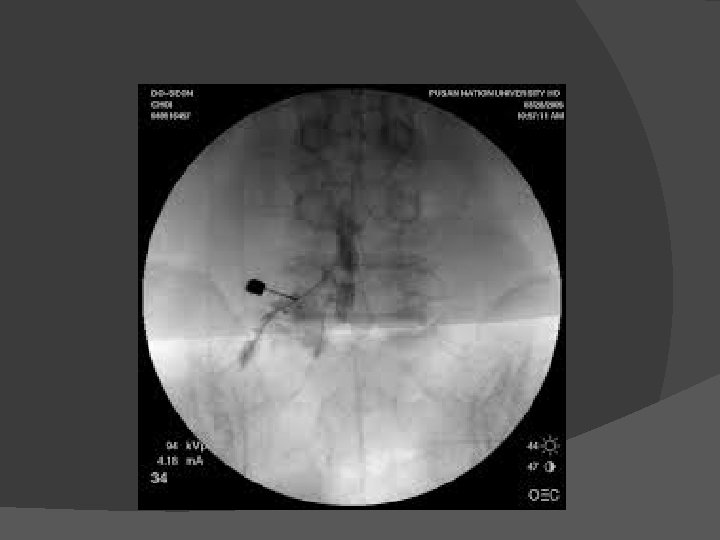

� Kasus 4 laki-laki, 27 tahun didiagnosis dengan adeno ca recti. Mengeluh nyeri disekitar anal selama 6 bulan. Sudah menjalani operasi dan kemoterapi. Selama ini mendapat terapi morfin oral namun masih mengalami nyeri dan mual muntah. Ganglion Impar neurolisis